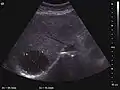

الفحص السريري للكبد يمكن أن يحدد حجمه ووجود المضض فقط، وقد تكون هناك حاجة أيضاً إلى بعض أشكال التصوير مثل الموجات فوق الصوتية أو التصوير المقطعي المحوسب.[51]

في بعض الأحيان يكون من الضروري إجراء خزعة للكبد، وأخذ عينة من الأنسجة من خلال إبرة يتم إدخالها عبر الجلد أسفل القفص الصدري مباشرة. يمكن أخذ الخزعة بتوجيه الموجات فوق الصوتية.[52]

تصوير البطن بالموجات فوق الصوتية (مقطع عرضي) يظهر تشمع الكبد مع تشكيل عقدي عند طفل عمره 3 سنوات.

تصوير بالموجات فوق الصوتية، تظهر تشمع كبد وحبن.